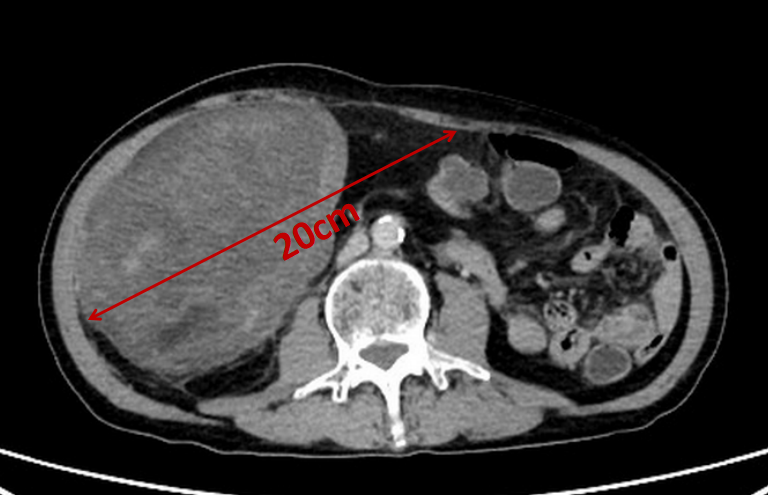

收入外二科后,郑志鹏主任带领团队迅速为患者完善腹部增强CT检查,确定腹膜后存在一个巨大肿瘤,上界达肝脏,下界至盆腔,贯穿了整个腹盆腔,压迫右肾、输尿管、膀胱及小肠,毗邻右侧腰大肌、腰方肌、腹主动脉、右侧髂血管及股神经。

肿瘤占据的空间非常大,看起来就像是患者肚子里藏了个“大西瓜”!

手术当天,经过3小时,郑志鹏主任团队顺利为患者完整切除肿瘤,术中基本无出血。 切除的肿瘤大小约32×20×15cm,重达8斤,病理检查显示为脂肪肉瘤。